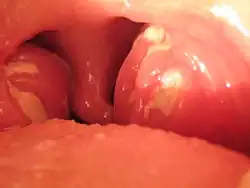

Choroba objawia się bólami głowy, złym samopoczuciem, utratą łaknienia, apatią, rozkojarzeniem, przewlekłym zmęczeniem, ogólnym osłabieniem. Następnie pojawia się gorączka, która z reguły wynosi 38-39 °C. Utrzymuje się ona przeważnie od dwóch dni do miesiąca i dłużej. Tuż przed jej wystąpieniem, w trakcie, rzadziej po jej spadku następuje powiększenie węzłów chłonnych, przede wszystkim na szyi i z tyłu głowy oraz angina. Stałym objawem jest również powiększenie śledziony i wątroby. Obrzęk śledziony może być tak duży, że niewielki uraz doprowadza do jej pęknięcia. Niekiedy rozwija się stan zapalny wątroby, prowadzący do żółtaczki. Typowym objawem dla mononukleozy jest obrzęk powiek. Czasami w przebiegu choroby może dochodzić do zapalenia płuc lub powikłań nerwowych, takich jak zapalenie mózgu i opon mózgowo-rdzeniowych, czy też nerwów obwodowych. Bardzo często występują punktowe, krwotoczne plamki na granicy podniebienia miękkiego i twardego.